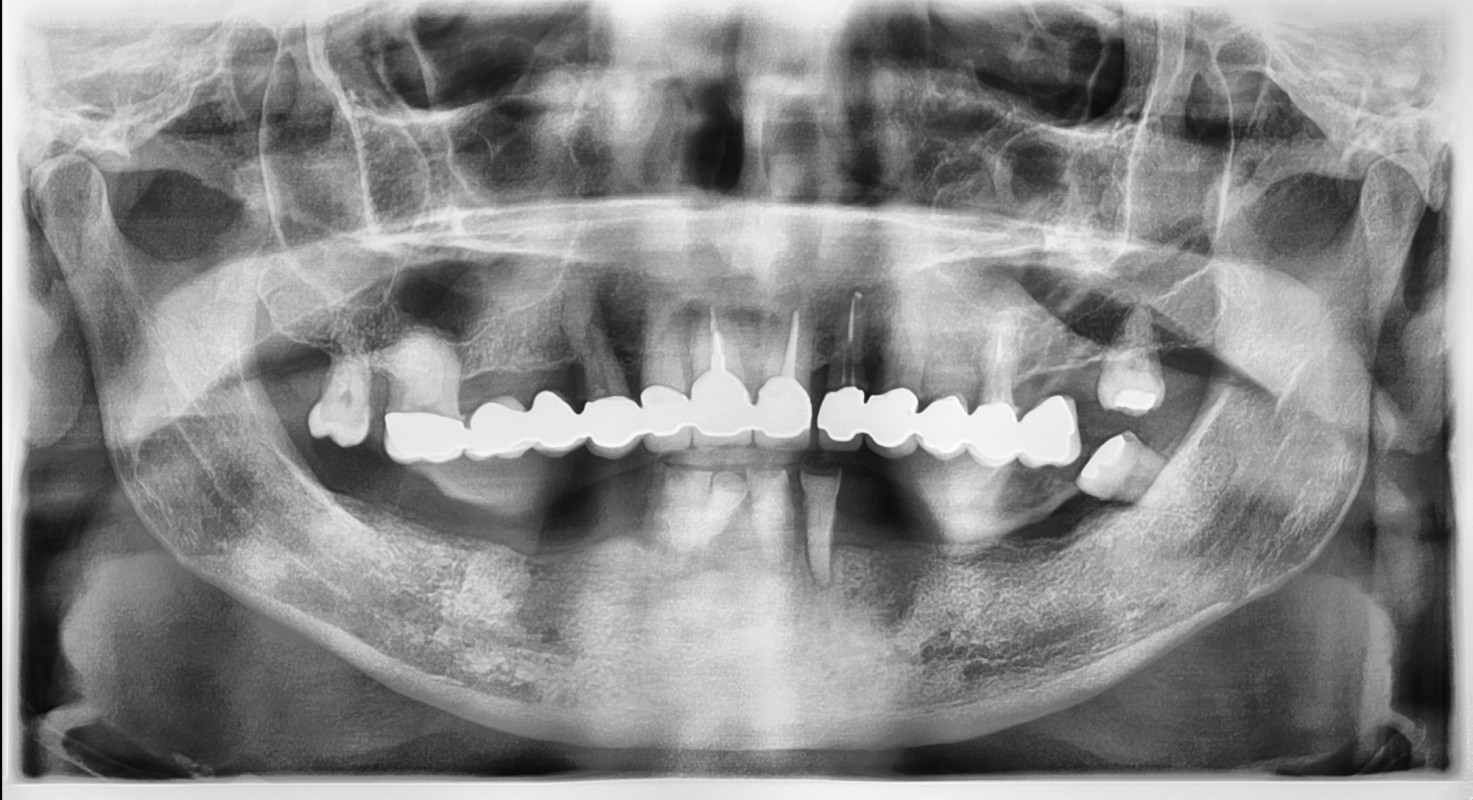

IL paziente presentava grossi problemi estetici ma soprattutto funzionali e di masticazione. Grazie agli impianti dentali a carico immediato e alla capacità dei nostri operatori ha risolto la situazione in una sola giornata (24 ore). La protesi che vedete infatti è stata creata e fissata in poche ore senza nessun dolore o fastidio. La sera stessa il paziente ha potuto tornare a sorridere e masticare fin da subito con denti fissi su impianti in una sola giornata cambiando nell'arco di poche ore la sua vita. Per ulteriori informazioni sulle tecniche di riabilitazione che quotidianamente eseguiamo e sulla possibilità di effettuare questo trattamento inviare una mail o contattarci direttamente in studio per fissare una visita con il dottore esperto nelle riabilitazioni con denti fissi in giornata.